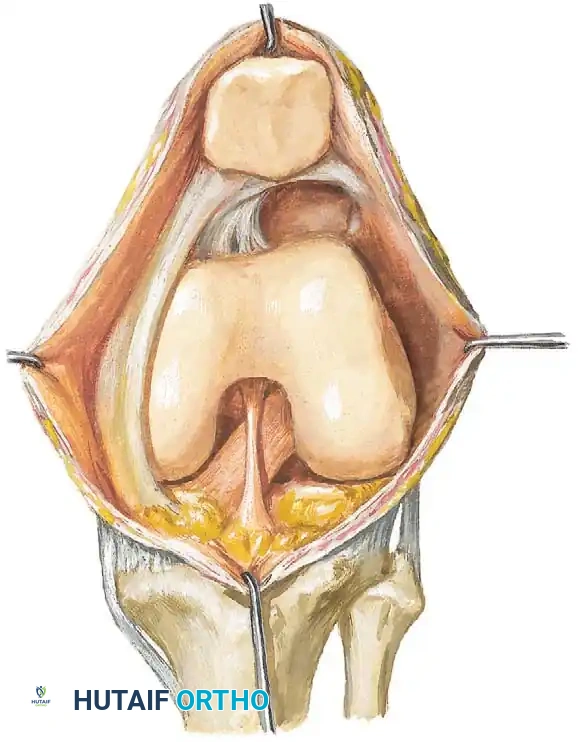

1. Infrapatellar Plica (Ligamentum Mucosum)

The infrapatellar plica is widely reported as the most common synovial plica. It originates from the intercondylar notch, runs parallel to the anterior cruciate ligament (ACL), and inserts into the infrapatellar fat pad. In an embryological study of 116 knees, Ogata and Uhthoff found that in fetuses between 11 and 20 weeks of age, an infrapatellar plica was present in 50% of specimens. While highly prevalent, it is rarely symptomatic but can obscure arthroscopic visualization of the ACL if significantly thickened.

2. Mediopatellar Plica (Medial Shelf)

The mediopatellar plica is the most clinically significant variant, frequently implicated in symptomatic plica syndrome. It originates from the medial wall of the joint capsule, courses obliquely downward beneath the medial retinaculum, and inserts into the infrapatellar fat pad. Medial patellar plicae have been reported in 5% to 70% of individuals. In a clinical series of 168 arthroscopic knee examinations of patients presenting with anterior knee pain, Calpur et al. identified 168 mediopatellar plicae, highlighting its strong association with clinical symptoms.

3. Dynamic Evaluation

With the arthroscope in the lateral portal, the knee is slowly taken through a range of motion from full extension to 90 degrees of flexion. The surgeon must directly observe the mediopatellar plica to confirm if it snaps over the medial femoral condyle or becomes trapped between the quadriceps mechanism and the trochlea at 70 degrees of flexion.

4. Excision Technique

- Instrumentation: A motorized oscillating shaver (4.0 mm or 4.5 mm) and an arthroscopic basket punch or radiofrequency (RF) ablation wand are utilized.

- Resection: Beginning at the free edge of the plica, the tissue is systematically resected. The resection must be carried down to the normal synovial base at the medial capsule.